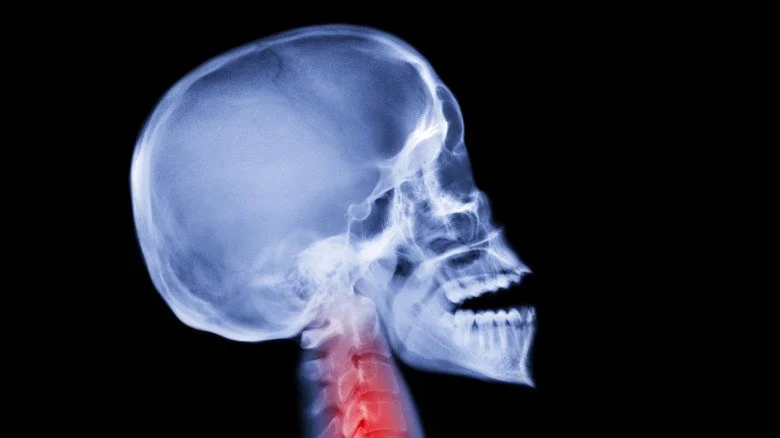

Fibrodysplasie ossifiante progressive

Radiographie du crâne de profil

Connue sous le nom de maladie de Münchmeyer, la fibrodysplasie ossifiante progressive est une maladie rare qui touche environ une personne sur un million. Elle résulte d’une mutation génétique qui entraîne une production excessive d’os et de cartilage dans les articulations, causant des douleurs intenses. Les symptômes se manifestent dès l’enfance et s’aggravent avec le temps, affectant notamment les muscles thoraciques et entraînant des difficultés respiratoires. La durée de vie des personnes atteintes est souvent réduite, avec une moyenne d’âge au décès autour de 40 ans, principalement due à des défaillances cardiorespiratoires.